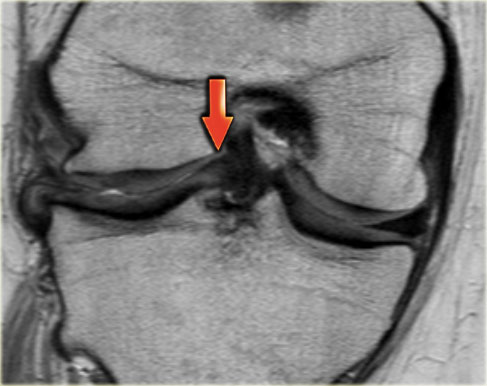

Trên hình ảnh mặt phẳng coronal, trước tiên sẽ thấy sừng trước to và phồng lên.

Ở phía sau sẽ thấy sừng sau rất nhỏ.

- Lưu ý sừng trước rất lớn.

Phần trong là sừng sau đã bị di lệch. - Phần trong chạy vào hố gian lồi cầu.

- Phần bị di lệch được nhìn thấy rõ ràng như là ‘cấu trúc thứ ba’

trong hố gian lồi cầu. - Điểm nối với phần còn lại của sừng sau.

- Điểm nối với phần còn lại của sừng sau.

- Phần còn lại rất nhỏ của sừng sau.